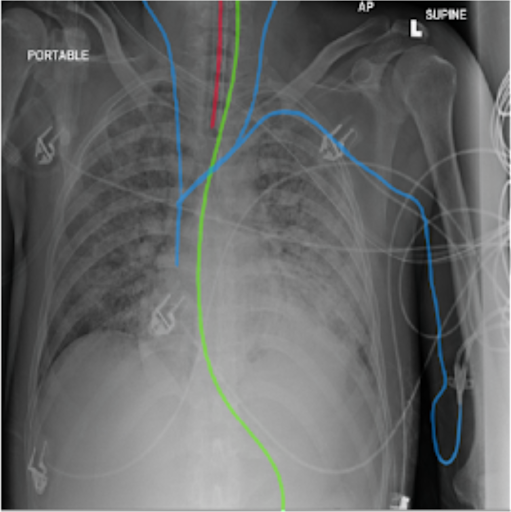

In March 2021, PFN were in third place out of 1,547 teams from around the world at a Kaggle competition RANZCR CLiP in which the participants competed for classifying presence and correct placement of tubes on chest x-rays (right image).

Image credit: NIH Clinical Center. Wang X, Peng Y, Lu L, Lu Z, Bagheri M, Summers RM. ChestX-ray8: Hospital-scale Chest X-ray Database and Benchmarks on Weakly-Supervised Classification and Localization of Common Thorax Diseases. IEEE CVPR 2017